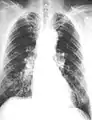

The abnormal chest x-ray and its interpretation remain the most important factors in establishing the presence of pulmonary fibrosis.[11] The findings usually appear as small, irregular parenchymal opacities, primarily in the lung bases. Using the ILO Classification system, "s", "t", and/or "u" opacities predominate. CT or high-resolution CT (HRCT) are more sensitive than plain radiography at detecting pulmonary fibrosis (as well as any underlying pleural changes). More than 50% of people affected with asbestosis develop plaques in the parietal pleura, the space between the chest wall and lungs. Once apparent, the radiographic findings in asbestosis may slowly progress or remain static, even in the absence of further asbestos exposure.[23] Rapid progression suggests an alternative diagnosis.

Extensive fibrosis of pleura and lung parenchyma.

Severe pleural fibrosis with focal calcification.

61 yr old working industrially with asbestos for decades.